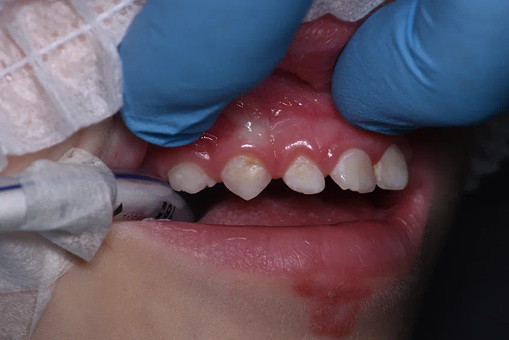

Лечение кариеса проводится следующим образом - сбор анамнеза, проведение местной анестезии, дентальный снимок (при необходимости), изоляция (коффердам), фотопротокол, удаление кариозных тканей (с использованием бора), антисептическая обработка полости, реставрация пломбировочным материалом, шлифовка, полировка.

До/после лечения